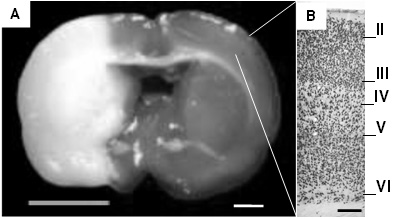

En este estudio se evaluaron de manera cualitativa los cambios en la región contralateral a la lesión de la corteza cerebral frontoparietal. Los resultados se obtuvieron con base en los datos aportados por los grupos de ratas experimentales confrontados con el grupo control y el análisis descriptivo de los cambios en la inmunoreactividad de las neuronas al NeuN. En todos los especímenes sometidos a isquemia y reperfusión se observó una lesión frontoparietal en el territorio de la ACM del tejido ipsilateral a la lesión, lo que comprende una pérdida de las características anatómicas e histológicas con grados de daño neuronal que van desde lesión evidente a las 24 h, hasta pérdida total del tejido con formación de zonas quísticas (Fig. 1), como lo hemos reportado en otros estudios 4,9,33.

Figura 1.

Corte coronal teñido con TTC después de isquemia cerebral focal y reperfusión con la técnica de filamento intraluminal. En A, se observa pálida el área de lesión que incluye corteza cerebral y ganglios basales. A la derecha se observa la corteza cerebral ampliada a 10X en la que se diferencian las neuronas marcadas con NeuN organizadas en láminas. Las observaciones descriptivas de todos los especímenes se tomaros del sector aproximado señalado en la imagen que corresponde a un corte coronal en Bregma 2,04 mm. (A barra= 2 mm, B barra= 250 μm).